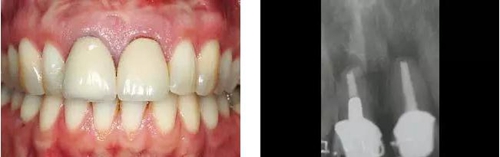

圖1、外形較大的雙側(cè)上中切牙唇側(cè)有瘺管,預(yù)后不佳,患者高笑線、薄齦生物型。

圖2、放射線片顯示雙側(cè)中切牙根尖均有感染病變。

圖8、植入2顆Camlog平行壁螺紋種植體,扭矩達(dá)35Ncm。安放兩個(gè)粗直徑的愈合帽,防止軟組織退縮和凹陷。

圖12、種植體植入后2個(gè)月取出愈合帽,可見(jiàn)牙齦外形和齦乳頭維持得相當(dāng)好。

圖13、安放全瓷基臺(tái)。

圖14、最終修復(fù)體就位,冠頸部較窄。沒(méi)有任何牙齦和牙齦乳頭的退縮。

圖15、種植體植入后12個(gè)月的微笑相。